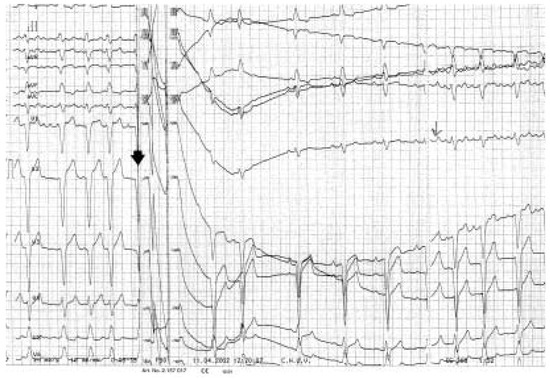

The definition of metabolic syndrome includes the presence of at least three of the following criteria: dyslipidaemia, hyperglycaemia, hypertension, and obesitas. The risk for cardiovascular events is strongly elevated in patients with metabolic synd...